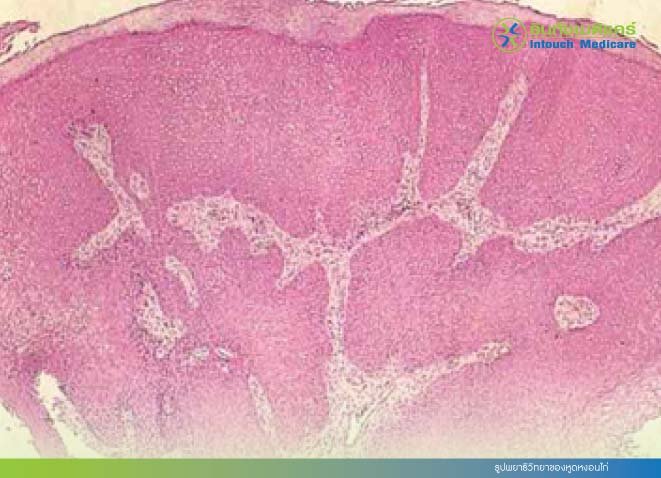

ภาพพยาธิวิทยาของหูดหงอนไก่

• เชื้อ HPV ทำให้เกิดการติดเชื้อใน epithelial cell ของผิวหนังและเยื่อบุเท่านั้น หลังการติดเชื้อไวรัส เซลล์จะมีการเปลี่ยนแปลง และเพิ่มจำนวนขึ้นเร็วจนเกิดเป็นเม็ดหูดขึ้น ทางพยาธิวิทยาพบว่าชั้นที่มีการหนาตัวอย่างมากจนทำให้เกิด papillomatosis คือชั้น malpighian layer

• ในชั้นนี้พบเซลล์ขนาดใหญ่จำนวนมาก มี vacuole ล้อมรอบด้วยนิวเคลียสที่มีลักษณะกลมและติดสีเข้มซึ่งเป็นลักษณะของเซลล์ที่มี cytopathic effect จากการติดเชื้อไวรัส

รูปพยาธิวิทยาของหูดหงอนไก่